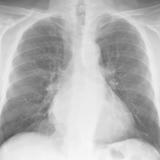

Heart failure

Album: Heart failure

Date: 11/05/2005

Size: 24 items

Views: 45881